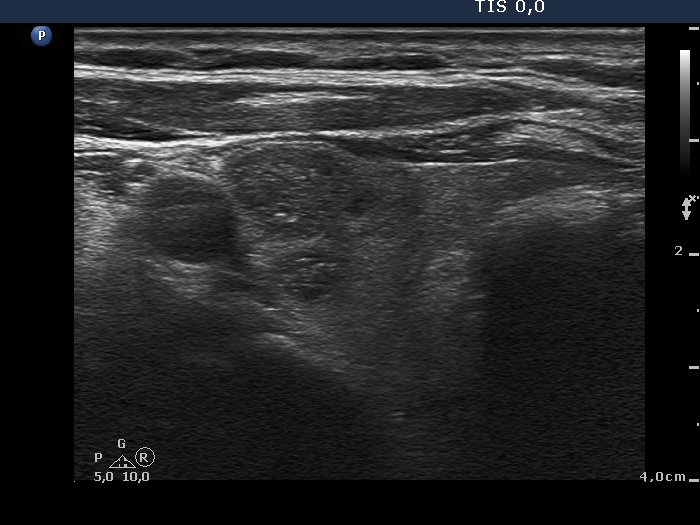

Study on 100 consecutive patients with thyroid nodule - case 066 (ultrasonographic picture 2)

Lower part of the right lobe, transverse scan. This is a nodule with a pattern similar to that presented in the previous image.